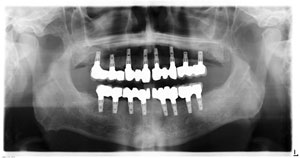

Dental implants are referred to as being substitute tooth roots or root replacements used to replace missing teeth. Dental implants are used for upper and lower teeth. They are placed within the bone and heal over a period of months to which then a crown is made and attached. Dental implants are made of the same biologically-compatible materials as artificial knees, hips or other prosthetic appliances. After the implant is placed, a period of time (usually 2-4 months) is required for it to fuse to the surrounding tissue and become anchored. A customized crown is then fabricated and attached to the implant.

Dental implants have been used for several decades. Patients of all ages have chosen dental implants to replace single or multiple teeth or even to support dentures. Dental implants give full function and support as natural teeth and are much stronger than natural or existing teeth. They are made of titanium and are compatible with the human body. Approved and tested dental implant systems are very successful.

We are proud to offer the most sought after dental implant procedures for our patients. Whether you need an implant to replace a single tooth or you require the placement of several implants to restore esthetics and function for multiple missing teeth (e.g., such as the newest full-arch implant replacement options including All-on-4® and Trefoil®, etc.), we can help. Our doctors have the most advanced training in implant dentistry available anywhere in the world. We specialize our treatment plans for your individual needs – no cookie cutter approach.